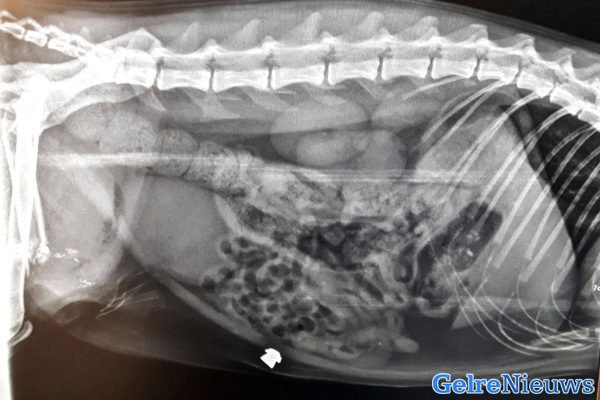

Het gebeurde vermoedelijk maandagavond tussen 18:30 en 22:30 uur in de omgeving van de Heumensebaan in Groesbeek door een nog onbekend persoon. Het kogeltje is dwars door de voorpoot gegaan en in de buik van de kat terecht gekomen. De poot van de kat Jackson is er zo slecht aan toe dat deze vermoedelijk geamputeerd moet worden.

Ruim een week geleden is er ook een kat beschoten in Dieren. Dit beestje werd twee keer beschoten waarbij de twee kogels nog in het lijf zat van het beestje.